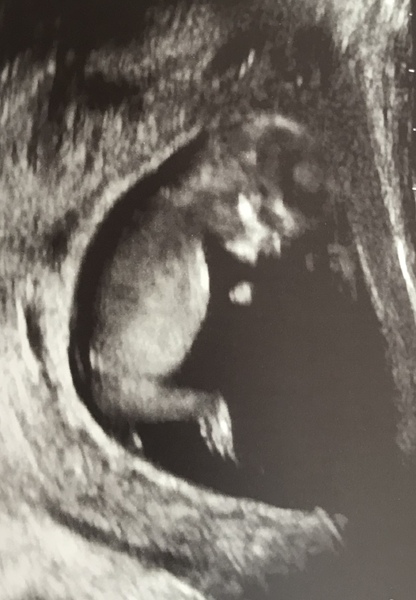

ohdearymemumof3 · 11/06/2019 15:30

Awww wow cant believe how clear some of these scans are so cute so jealous I really cant wait for mine! 6 days and counting

Ohhh gorgeous scans girls!! 😍😍

@ohdearymemumof3 going by the nub I'd say girl too 💓

I've seen a few people mention about a nub I was new to this haha but I have no idea what is a nub ?

Comps83, great scan pic! You can see everything clearly in the pic. What’s the three day wait? Is it for bloods?